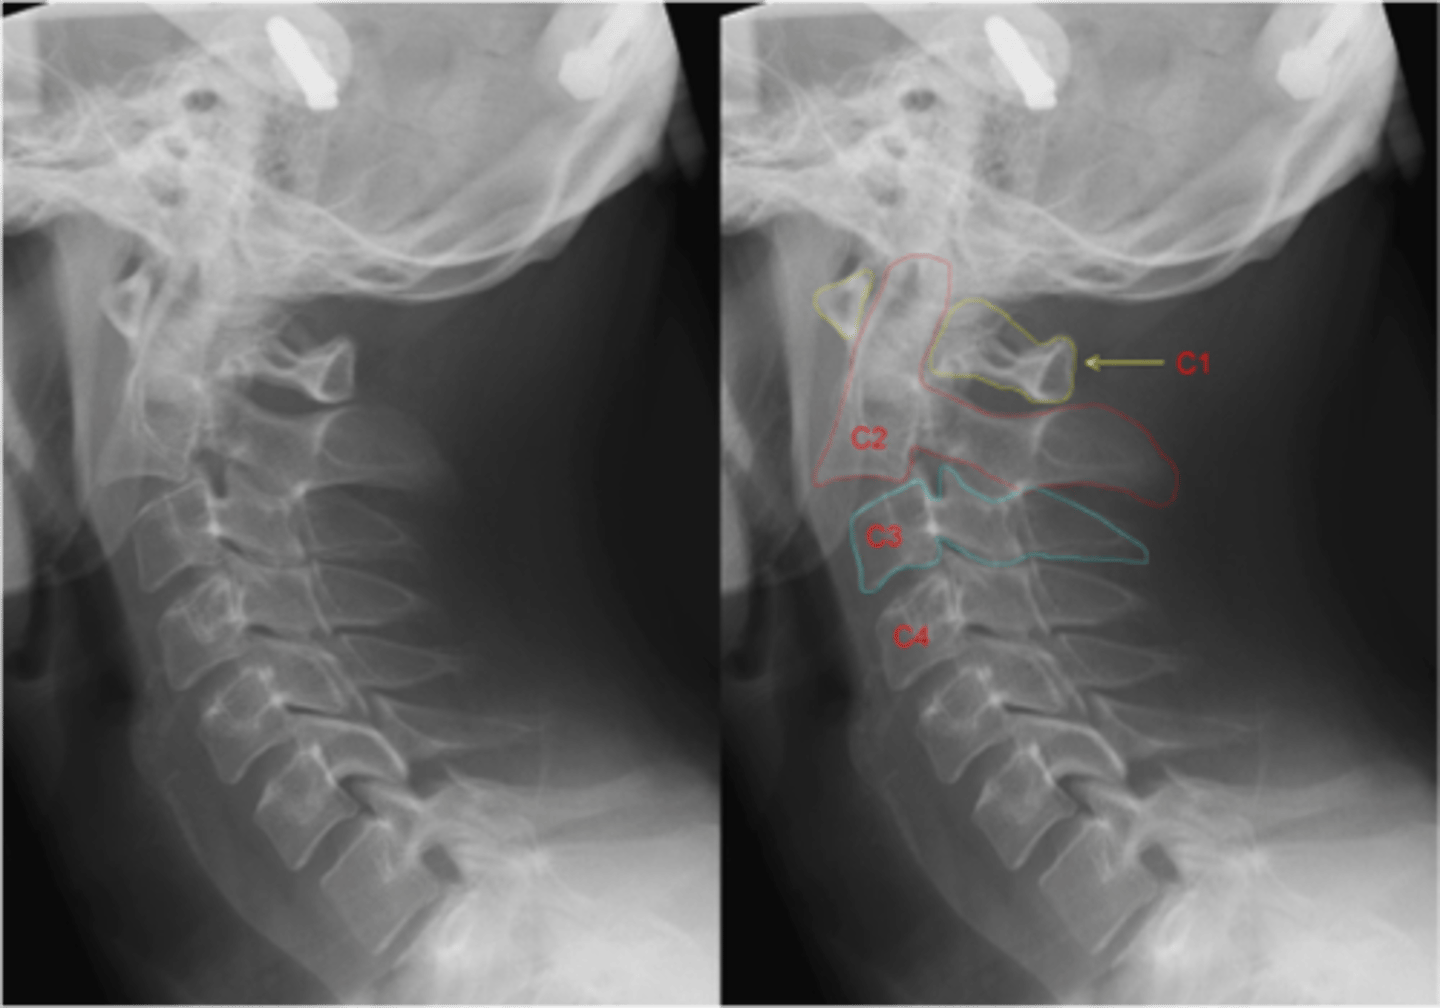

hangman's fracture is a fracture of the

bilateral pars interarticularis of C2

hangman's fracture is traumatic _____ of the atlas/axis

spondylolisthesis of the axis (C2)

what are the most common causes of a hangman's fracture

MVA, diving injuries, sports injuries, face first fall from standing position

Jefferson's fracture is a ___ fracture of the atlas/axis caused by axial loading of the cervical spine

burst fracture of the atlas (C1)

are jefferson's fractures usually accompanied by c-spine injuries?

yes, 1/3 have c2 fracture

Jefferson's fracture also usually causes a blunt ____ injury

cerebrovascular (ICA, CCA, vertebra artery)